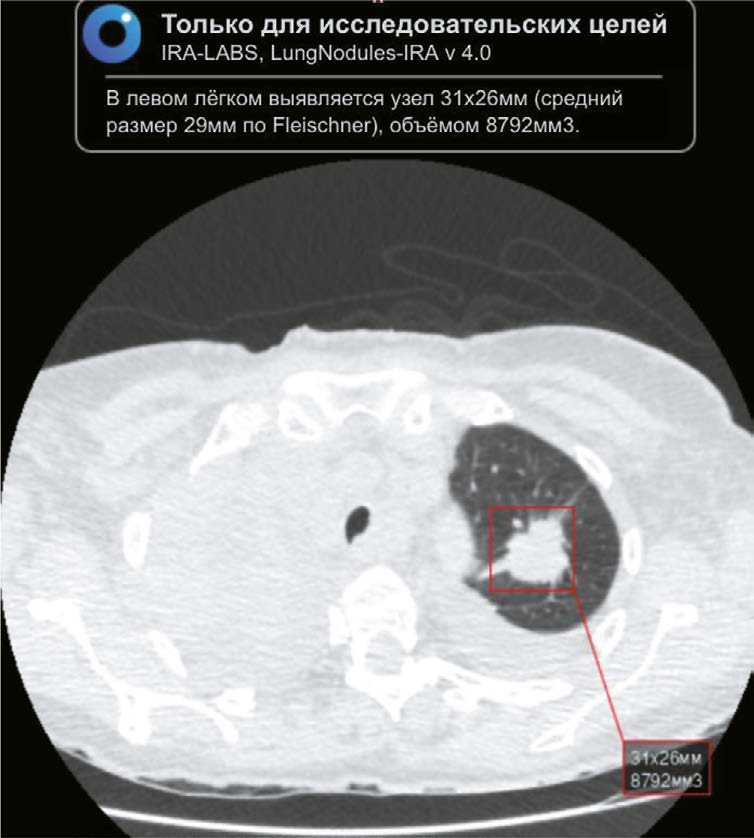

BACKGROUND: Chest computed tomography (CT) is the main modality used to diagnose lung lesions caused by COVID-19 infection. Since 2020, the use of this modality in the Krasnoyarsk krai has increased. However, the incidence of lung cancer decreased by 5.2%. The current situation has raised concerns about missing radiographic signs typical of lung cancer and has stimulated the search for new diagnostic modalities using artificial intelligence (AI) for data analysis.

AIM: The aim of the study was to evaluate the feasibility of using an AI algorithm to search for lung nodules based on chest CT data obtained during the COVID-19 pandemic to identify lung cancer.

MATERIALS AND METHODS: The retrospective study included chest CT scans of patients from Krasnoyarsk krai diagnosed with COVID-19 reported in the PACS base between 1 November 2020 and 28 February 2021. The interval between chest CT and AI analysis ranged from two years and one month to two years and five months. Chest-IRA algorithm was used. AI detected lung nodules with a volume greater than 100 mm3. The radiologists divided the results into three groups based on the potential for lung cancer. The assessment of the economic benefits of using the AI algorithm considered the cost of wages and savings in the treatment of early stage lung cancer, which affects gross regional product.

RESULTS: The AI algorithm identified nodules in 484 out of 10,500 CT scans. A total of 192 patients with a high potential for lung cancer, 103 with no signs and 60 with inconclusive signs were identified, and 112 patients with a high and moderate potential for lung cancer did not seek medical care. AI confirmed 100 (28.2%) histologically proven cases of lung cancer, with stages I–II detected in 35%.

Using AI instead of radiologists would save 25 months and 4 days of work, which is equal to 2 million 430 thousand rubles. Expected budget savings due to early detection of lung cancer vary from 10 million 600 thousand to 12 million 500 thousand rubles for each 10,500 CTs. The total economic effect for a five year period would be from 259 million 400 thousand rubles to 305 million 100 thousand rubles.

CONCLUSIONS: The use of AI to evaluate chest CT scans demonstrates high performance in identifying lung nodules, including those in patients with COVID-19, confirming its potential use for early detection of incidental lung nodules that might otherwise be missed.